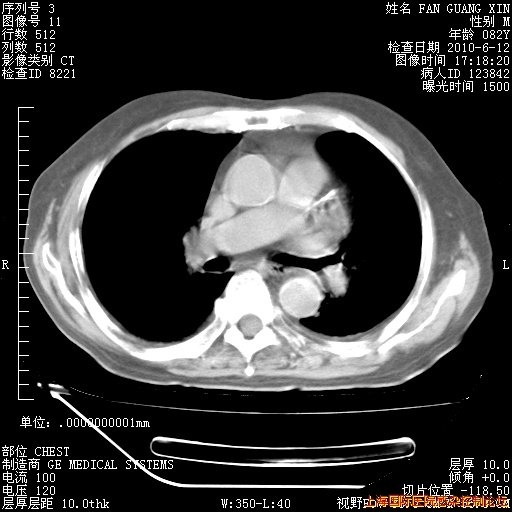

今天复查CT

今天CT

整整相隔30天的肺部CT好像有所好转啊。甲强龙减量第3天,需要观察体温。